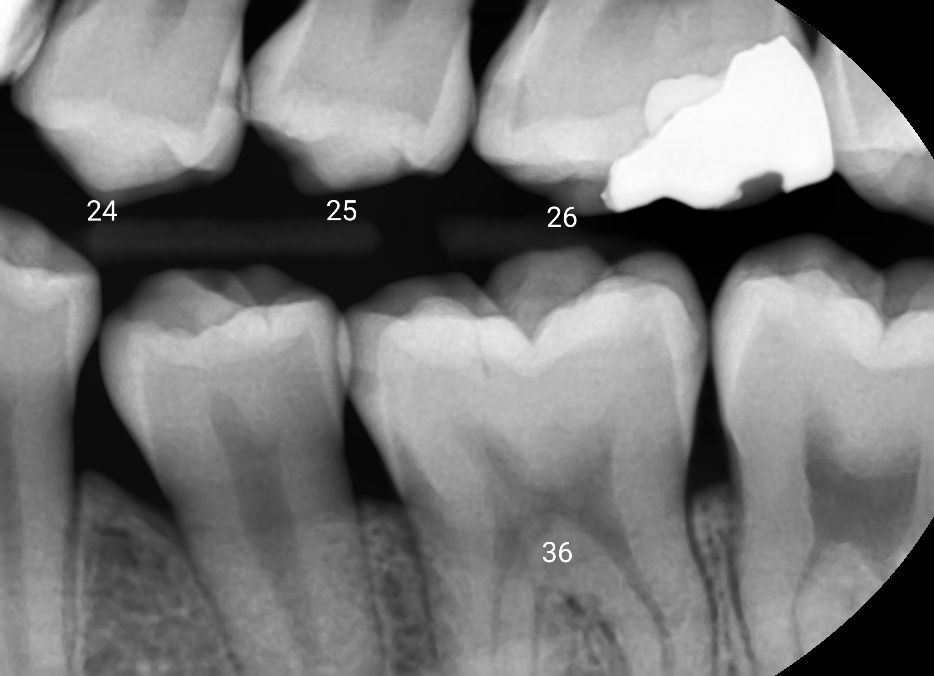

사진상으로 보면 2425번 사이 25 26사이에 인접면 충치가 잇는거 같고 36번 앞뒤로 치아 사이에 충치가 잇는것같습니다.

사진을 봤을때는 24, 25, 26, 36 치아에 인접면충치가 있는것으로 보입니다.

충치의 여부는 방사선 사진으로만 확인하는 것이 아니라 육안으로도 확인을 해야 하기 때문에 방사선 사진만으로 어떤 치료를 할지 결정하는 것은 어려운 일입니다.

치아의 인접 면에 충치가 생겼을 경우에는 치아의 모양을 만들기 힘들기 때문에 인레이 치료를 하는 경우가 많습니다.

주어진 사진만 봐서는 정확한 진단은 어렵지만 24번 원심(뒷쪽), 26번 근심(앞쪽), 36번 근심(앞쪽)이 '의심'됩니다.

인접면 충치는 우선 추천되는 것은 인레이이고 레진은 치료에 다소 한계가 있을 수 있습니다.